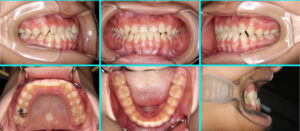

[38] 叢生・こどもの矯正

ガタガタ、受け口(叢生・Ⅰ期治療の途中・反対咬合) 治療前 治療中 治療の詳細 主訴 前歯の嚙み合わ[...] 本文を読む

[37] 子供の矯正治療

こどもの矯正治療(叢生・Ⅰ期治療の途中) 治療前 治療中 治療の詳細 主訴 前歯の反対咬みと受け口か[...] 本文を読む